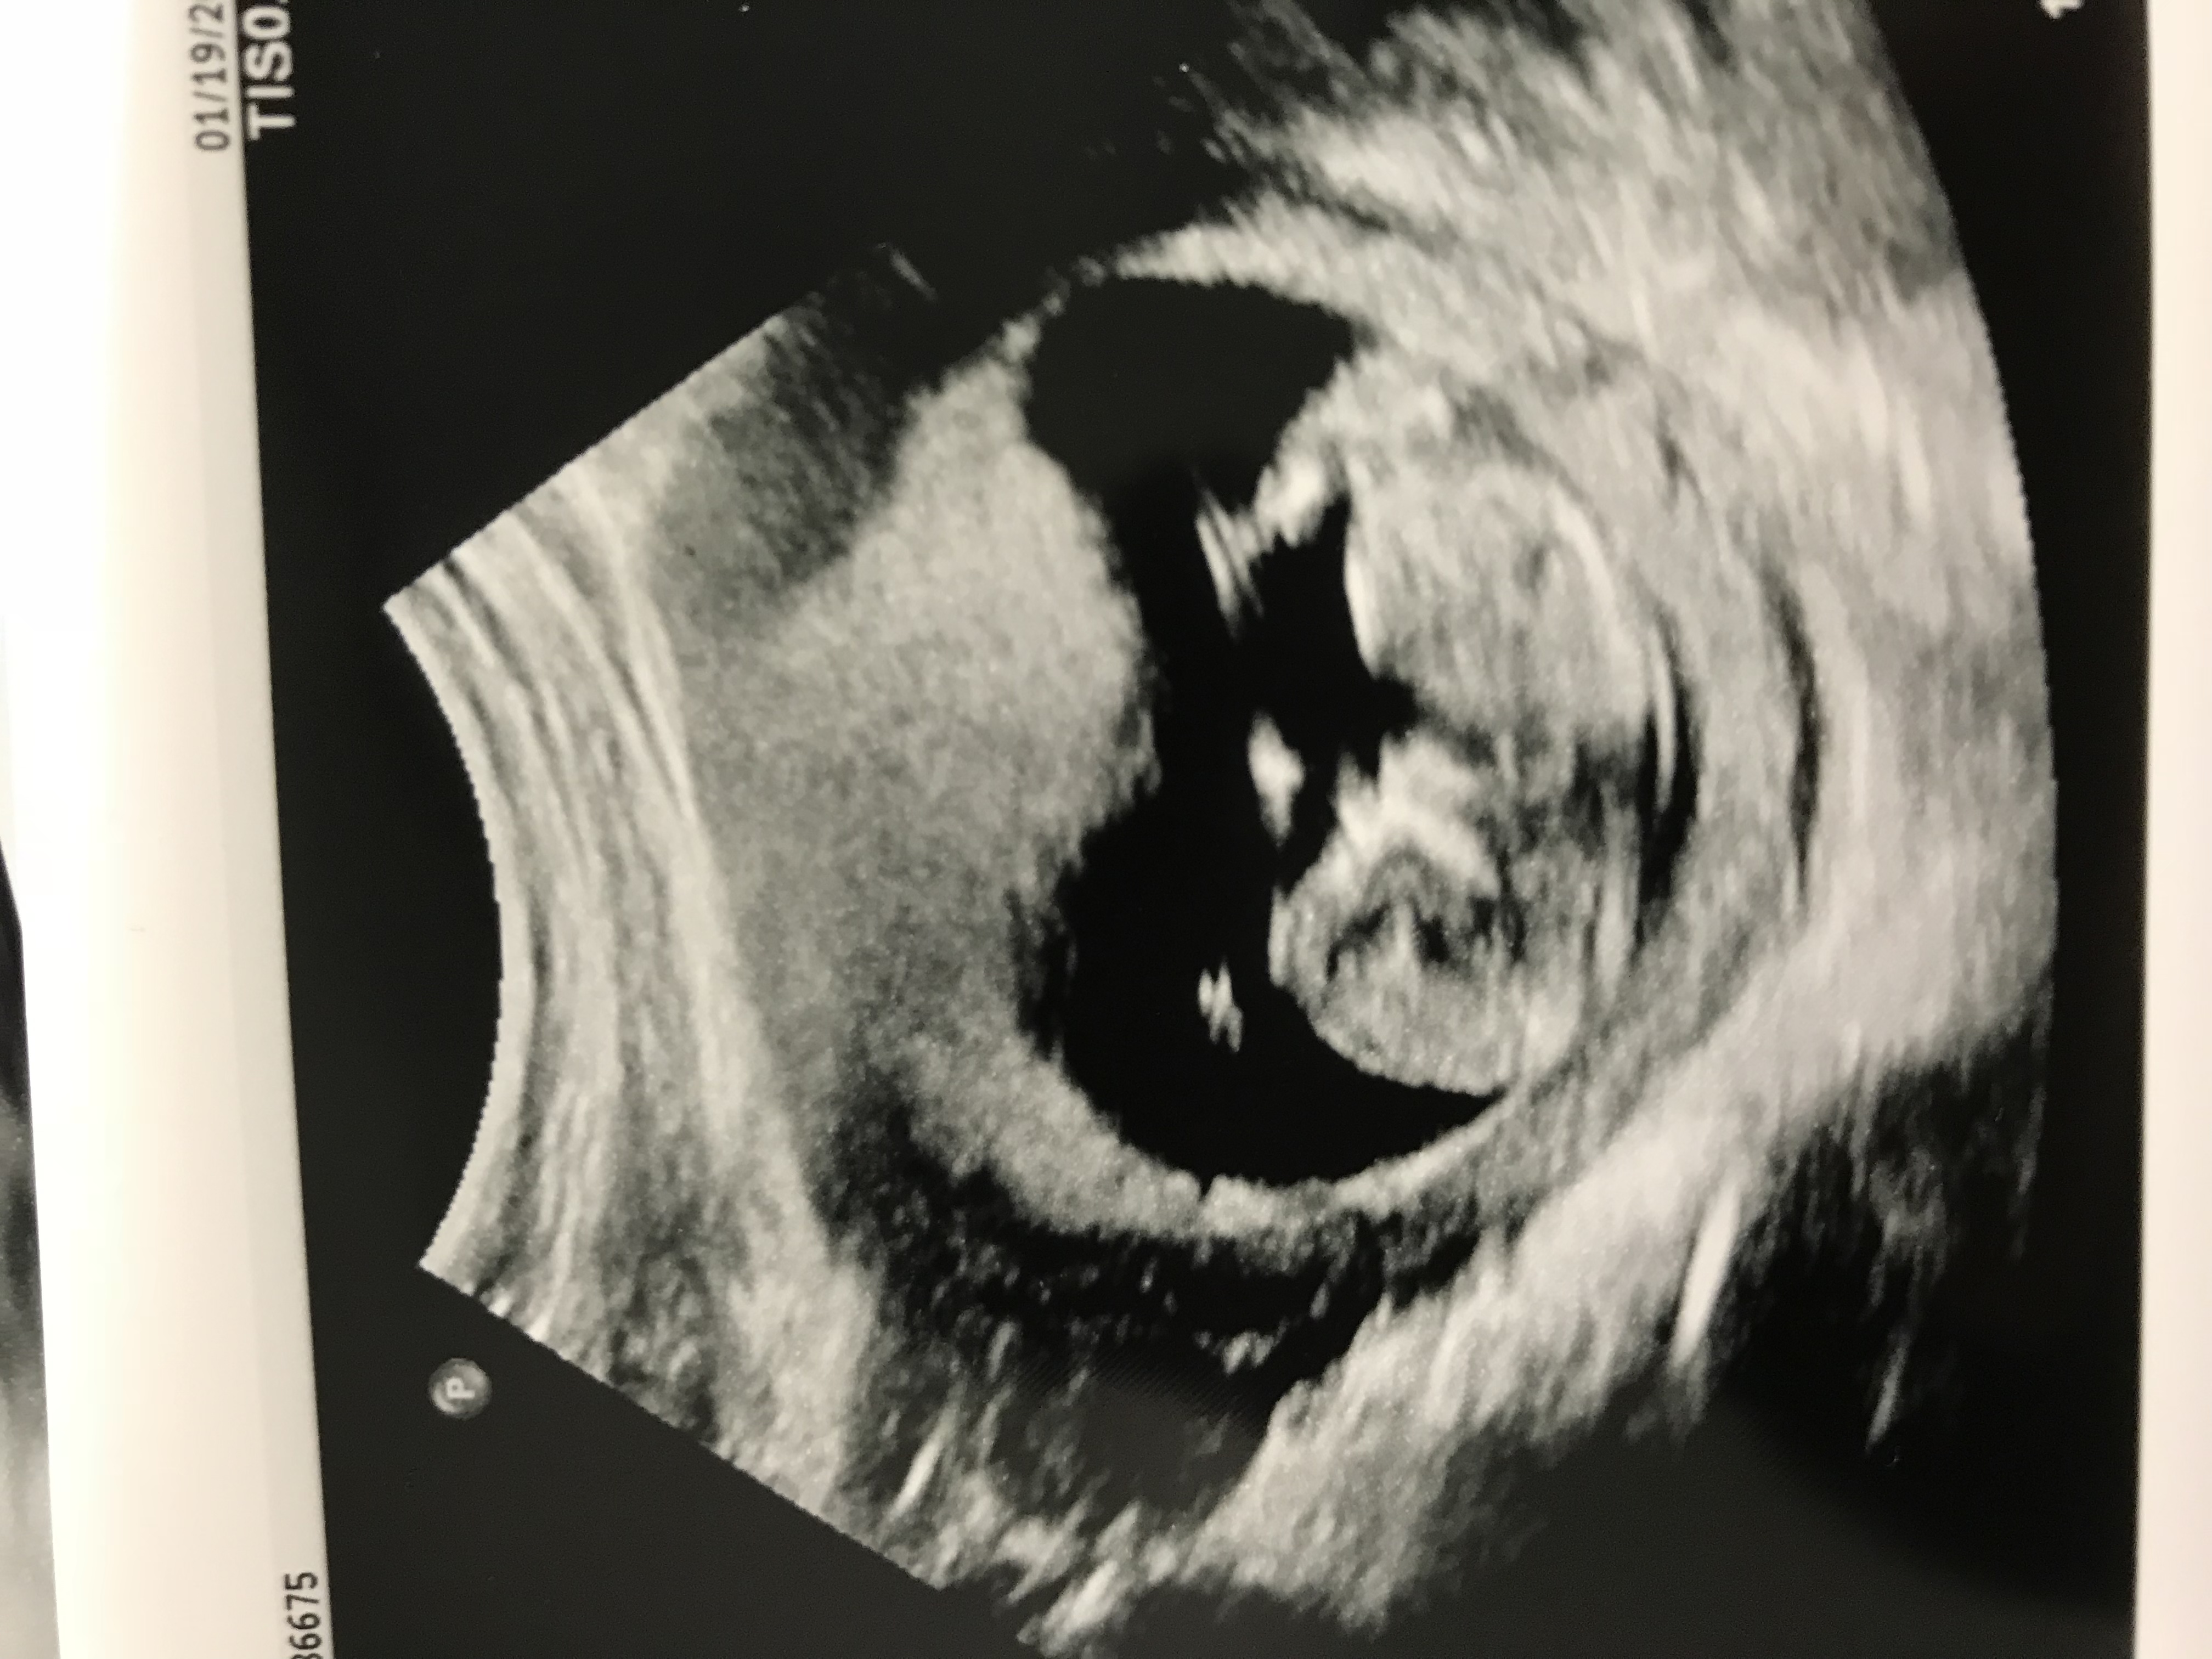

No picture of the nub. Was Hoping someone on the forum understood skull theory better than me. According to what I read I guess I’m leaning boy.